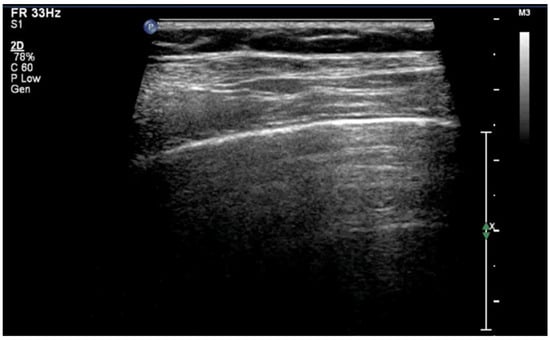

The “lung point” or “lung point sign” is a highly specific lung sonographic sign which helps in the diagnosis of pneumothorax and can also facilitate the assessment of pneumothorax severity. In particular, the severity of pneumothorax depends on its position relative to the anatomical lines that define the regions of the chest. In LUS, the “lung point” is defined as the boundary between the area without normal lung sliding (i.e., pneumothorax) and the area where normal lung sliding is present (normal lung) (Figure 8) [4,12,15,16,25,26].

Figure 8.

Lung point sign: The transition point between the aerated lung with coalescent B-lines (which probably represents respiratory distress syndrome) which are absent in pneumothorax and the area with A-lines (transparent arrow) but without lung sliding (absent in pneumothorax in real-time scanning).